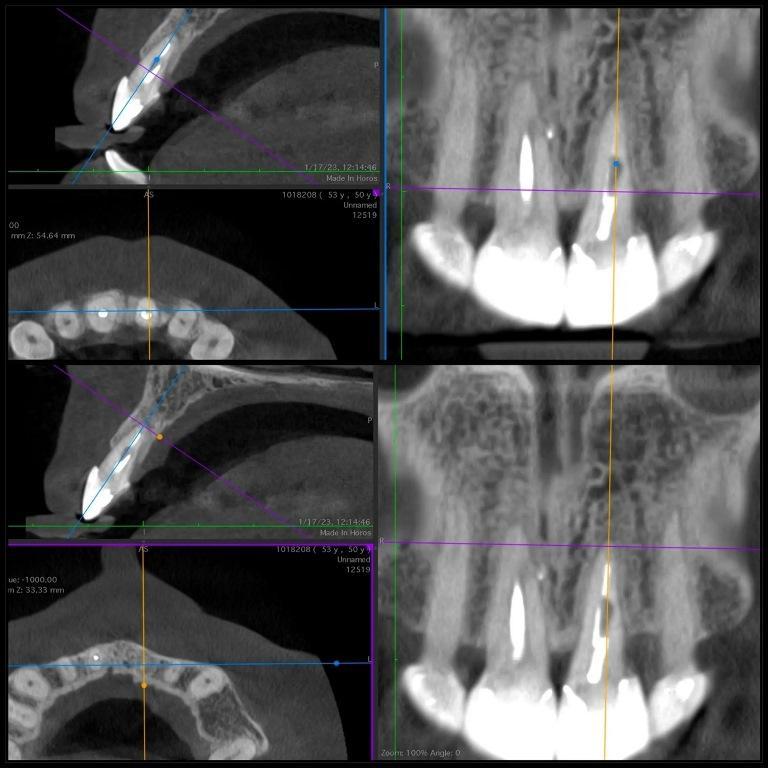

Рентгенологическое исследование, проведенное через два года после экструзии, выявило хорошее периапикальное заживление и продолжающийся вертикальный рост кости на межзубном гребне, главным образом в дистальной области (фото 5). Сообщалось, что нормальный контур периодонтальной связки может наблюдаться через три месяца после операции, а периапикальное восстановление и восстановление рентгенопрозрачности обычно наблюдаются через шесть месяцев, а также минимальная потеря костной массы, часто связанная с повреждением кости в процессе экструзии. Через два года наблюдалось полное восстановление периапикальной ткани и продолжающееся ремоделирование кости, главным образом в области дистального гребня (фото 6). Зуб остается бессимптомным, немобильным и полностью функциональным с эстетической и биологической точек зрения (фото 7). Рентгенологическая картина после четырехлетнего периода наблюдения показала стабильные результаты (фото 8).

Фото 6: Последующее двухлетнее КЛКТ-сканирование показало полное заживление периапикальной области, ремоделирование кости в дистальной области и отсутствие признаков резорбции.